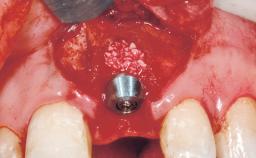

A 42-year-old female patient was referred to our clinic at the School of Dentistry of the University of São Paulo in November 2004, presenting a deficient restoration in the upper left central incisor. The clinical examination revealed no gingival retraction or any signs of gingival inflammation and, therefore, previous periodontal treatment was not considered. The patient presented a high lip line at full smile and a thin tissue biotype. This combination characterized a high-risk situation from an anatomic point of view, which required careful preoperative planning and cautious surgical execution.

Type of Implants One-Piece

Placement Protocol Immediate implant placement

Socket Integrity Sufficient, with intact bone walls

Bone Volume Sufficient, with intact walls